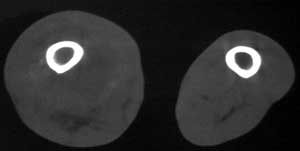

男56涨疼5-6月

右股骨下端包绕股骨见巨大软组织肿块,密度部俊,周围见瘤骨,下端骨皮质侵蚀变薄,骨质周围无骨膜反应, 考虑右股骨软骨肉瘤。

右股骨下段周围软组织肿块伴钙化,相邻股骨骨皮质受累,考虑软组织来源恶性病变

右股骨下段骨肉瘤,软组织内瘤骨,软组织肿块。